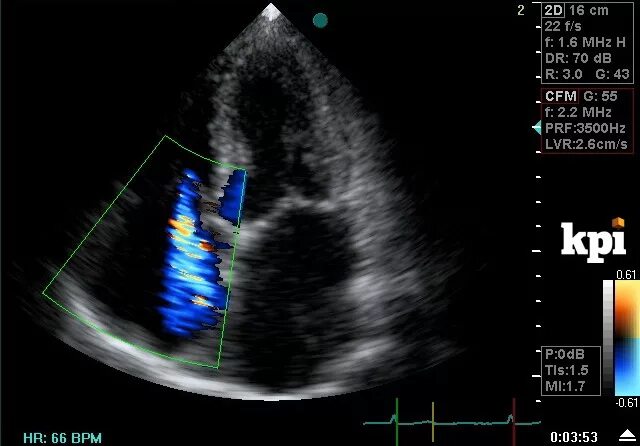

Узи сердца показывает сердечную недостаточность